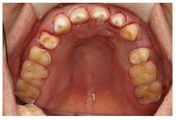

(1)面部检查:面部外形不对称,颏部居中,两侧口角高度不一致,面下1/3高度减小,两侧颧弓突度一致,下颌前突。中位笑线,上唇长度适中(图1)。(2)关节检查:颞颌关节:弹响(-),杂音(-),疼痛(-)。开口度正常,开口型有偏斜,肌肉触诊压痛:右侧上颌结节(+)、左侧上颌结节(++)、双侧翼内肌(+),其他肌肉及颞下颌关节区未诉异常,关节载荷实验无任何紧张和疼痛不适。(3)口内检查:上下颌牙中线较面中线向右偏斜,前后牙广泛不均匀磨耗,前牙磨耗后呈刃状;14、21、22、23及下颌牙唇颊侧颈部见釉质缺损,部分牙本质暴露,呈黄褐色,少量白垩色;44牙见开髓孔,表面暂封。12缺失,缺失牙间隙无。全口牙龈色形质未见异常,11牙、21牙唇侧牙龈龈缘高度不一致,21牙较11牙龈缘高约3mm。全口口腔卫生状况良好,菌斑、软垢少量,未及牙石及牙周袋。咬合检查:11-14牙与对颌牙反

,21牙与31、31牙对刃,左侧尖牙至前磨牙深覆盖,

曲线不平(图2,图3)。(4)影像学检查: